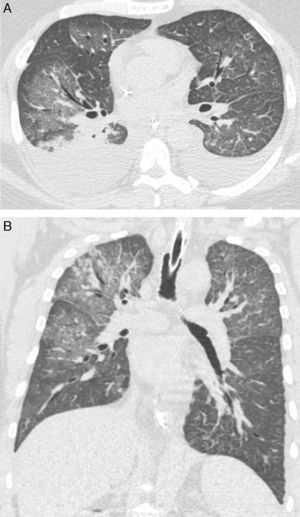

Hemos realizado una revisión retrospectiva de las historias clínicas de 8 pacientes adultos con síndrome pulmonar por Hantavirus (SPH) confirmado, con el fin de describir los hallazgos en las pruebas de tomografía axial computarizada de alta resolución (TACAR). Los pacientes fueron atendidos en 6 hospitales terciarios de Brasil entre los años 2003-2014. Los diagnósticos de SPH estuvieron basados en la historia clínica, el curso clínico y los hallazgos en las pruebas de imagen de cada paciente. Las pruebas serológicas (ELISA) de todos los pacientes mostraron resultados positivos para Hantavirus. Aunque las características observadas en la TACAR de la infección por Hantavirus del Viejo Mundo son bien conocidas, no conocemos ningún estudio que haya analizado los hallazgos en la TACAR en pacientes con SPH. En nuestro estudio, las características principales de la TACAR fueron la presencia de opacidades en vidrio esmerilado (OVE) y de un ligero engrosamiento de los septos interlobulares, que se observaron en todos los pacientes (fig. 1). Sin embargo, el patrón en adoquín desordenado solo se observó en 3 casos. Se detectó derrame pleural y engrosamiento peribroncovascular en 5 casos. Cuatro pacientes presentaban nódulos pequeños, y solo uno mostró focos de consolidación. Las anomalías fueron bilaterales y difusas en todos los casos.

Para concluir, los hallazgos predominantes en la TACAR de pacientes con SPH fueron las OVE y un ligero engrosamiento septal. Estos hallazgos son de gran ayuda para el diagnóstico en un entorno clínico adecuado. El derrame pleural y el engrosamiento peribroncovascular también son hallazgos frecuentes, aunque menos característicos.